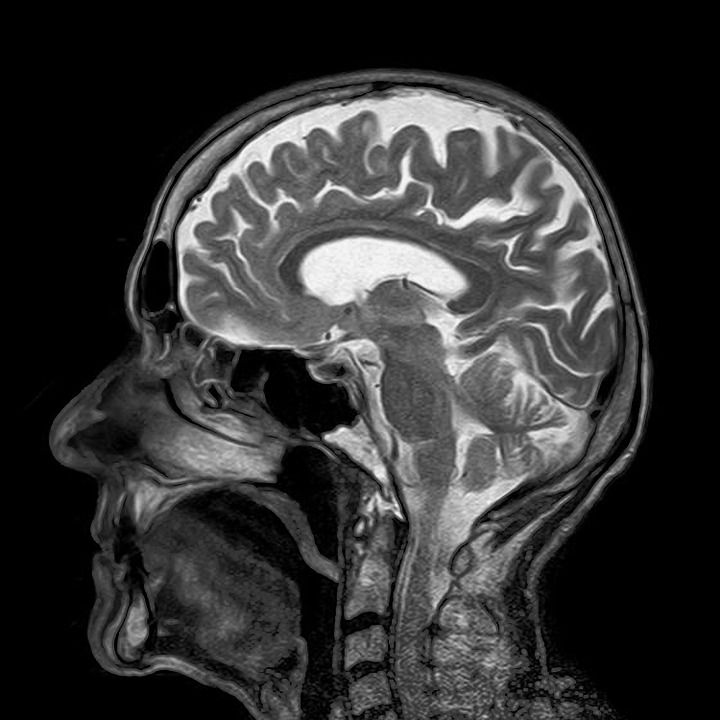

ちょっと先生の話からは脱線しますが、脳外科医は頭蓋骨を穿頭、開頭し、硬膜を切れば、脳を実際にこの目で見ることができます。

しかし、皆さんがMRIやCTで脳の断面を見たり、脳の構造を見るようには、脳外科医は肉眼では脳実質を構造的につかめません。

脳実質の内部の構造や脳神経なんてものは、本当に未知の世界でもあり、これから研究を進めていかなければなりません。

どちらにしても、脳内で起こっていることは、どんな名脳外科医であっても、見えていないわけです。